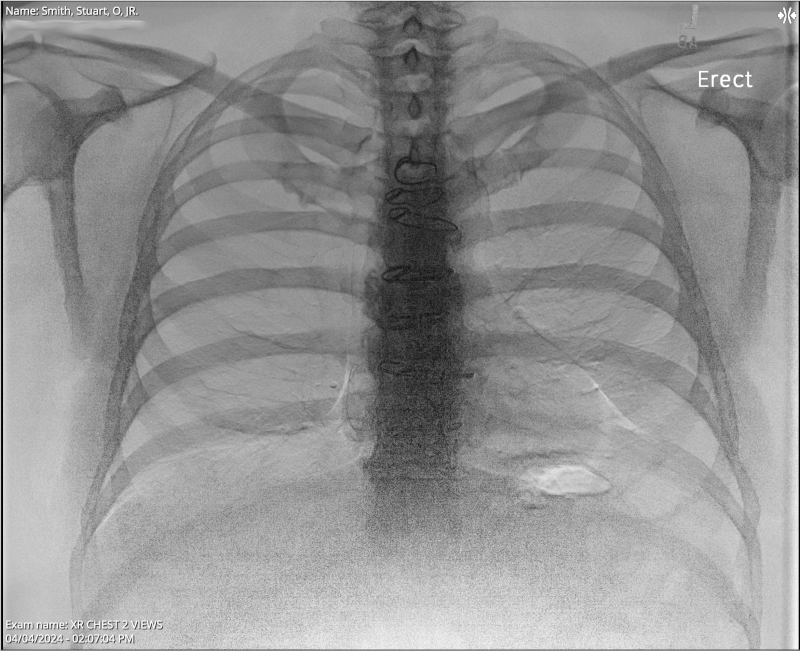

Chest X-ray

XR Chest 2 view Collected on April 5, 2024 7:42 PM . . . Impression 1. No evidence of acute cardiopulmonary process. . . . ORDERING CLINICIAN: EIRAN GORODESKI FINDINGS: Median sternotomy wires present. CARDIOMEDIASTINAL SILHOUETTE: Cardiomediastinal silhouette is normal in size and configuration. LUNGS: Lungs are clear. ABDOMEN: No remarkable upper abdominal findings. BONES: No acute osseous changes.

The results from my April 4, 2024, chest x-ray looked good. I still find it strange to view my x-rays and see some of the hardware that was left inside me after my April 27, 2023, septal myectomy (open-heart surgery) for Hypertrophic Cardiomyopathy. The notes above mention "Median sternotomy wires present," plus I also have retained epicardial pacing wires left inside me, which I have seen in other x-rays.

If you look very closely at the x-ray photo at the top of this blog post, and the following two x-ray photos, you can see the sternotomy wires: